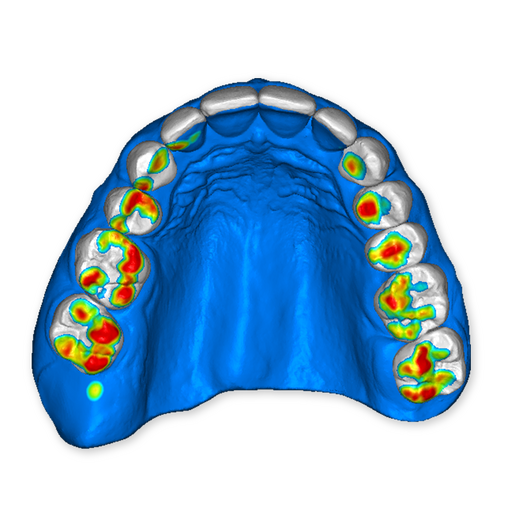

The DSD Interdisciplinary is a digital wax up of the upper and lower arches, designed considering a facially-driven, clinical and functional analysis of the patient.

It is our most comprehensive planning option, and includes all the 3D treatment simulations needed for each case, such as ortho, perio, implants, grafts and orthognathic surgery.

Our 3D simulations showcase facilitate a deeper understanding of the required procedures. This leads to the creation of a broader treatment plan and enables a more efficient communication with your patients.